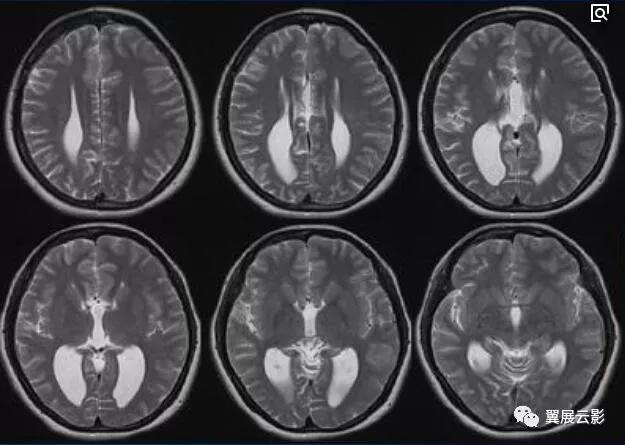

肾上腺脑白质营养不良

本病为一种遗传性疾病,由于患者细胞内氧化体内异常,导致脂肪代谢紊乱,体内长链脂肪酸异常增多,本病同时累及脑组织和肾上腺,脑的主要病理改变为顶,枕及颞叶脑白质出现对称性脱髓鞘改变,随着病程的进展,脑的受累区可更加广泛,肾上腺的改变为萎缩或发育不全,本病好发于3—12岁儿童,早期症状为智力减退,随即可出现视力减退,共济失调,听力障碍,抽搐,皮肤色素沉着及低血压等症状。

MRI平扫可见双侧侧脑室三角区周围白质区对称性大片状长T1长T2异常信号,胼胝体压部亦可呈现长T1长T2异常信号,将两侧大脑半球病变连接成蝶翼状改变,增强扫描病灶边缘部分可见花边样强化,中央部通常无强化,随着病程的延长,脑白质病变又后向前发展,范围逐渐扩大。本病特征性影象表现为双侧侧脑室三角区或枕角周围对称性脱髓鞘,并由胼胝体压部连接成蝶翼样改变,随着病情发展,病变由后向前扩展,上述征象有助于本病与其他脱髓鞘疾病的鉴别。